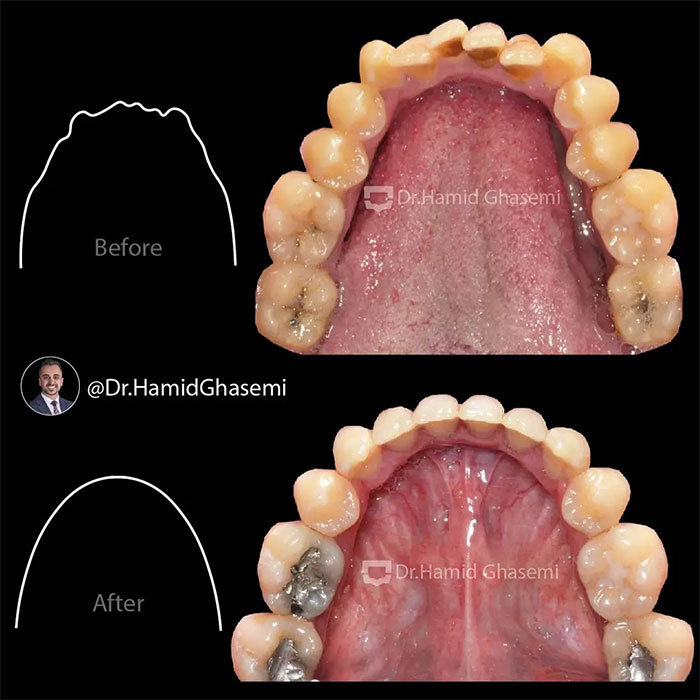

شماره پرونده : M.97_1321

درمان ارتودنسی همراه با جراحی هر دو فک در کیس open bite + long face در مدت ۲۴ ماه انجام شد. دندانهای نیش فک بالا جایگزین دندانهای غایب لترال شدند.

Orthodontic treatment with surgical procedure on both arches done for long face + open bite case within24 months. Upper canines substituted for missing upper laterals.